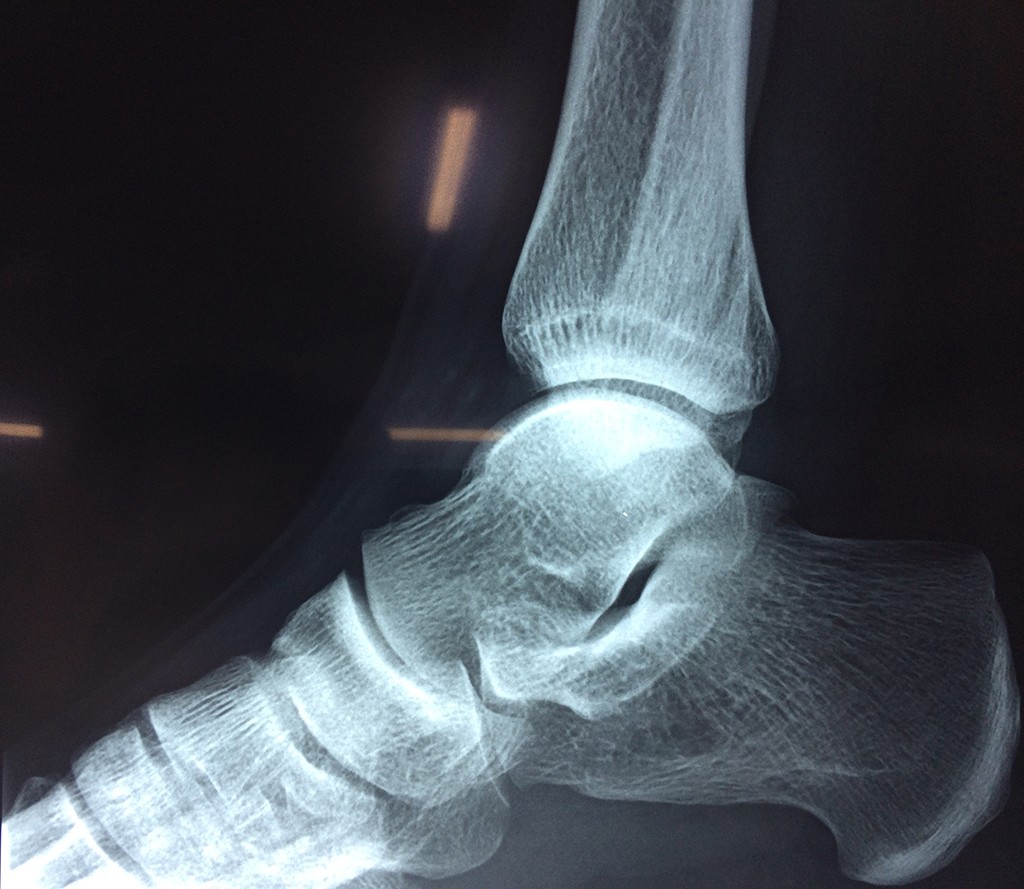

Una fractura de tobillo es la rotura de uno o más de los huesos del tobillo. Estas fracturas pueden ser:

• La fractura se extiende hasta la articulación del tobillo (fractura intra-articular).

Astrágalo Tobil...